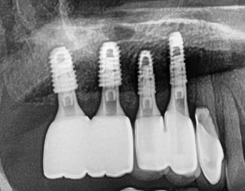

『4개월만에 완성』

4개월간의 f.u

디지털 진단 결과에 따라서,

임플란트 4개를 심어드렸으며

뼈이식까지 했으니 충분히

휴식 시간을 줘야 됩니다.

뼈와 잘 아물어야 높은 교합력을

내서 맛있는 음식을 드실 수 있을테니깐요.

그래서 사진에서 보시는 것 처럼,

4개월 가량을 기다려서 뼈와 잘 아문것을

확인했고 이어서 지르코니아 크라운 및

PFM 크라운을 연결해드렸습니다.

앞쪽에 있는 2개의 크라운은 PFM 이며,

뒤에 있는 2개는 지르코니아 크라운입니다.

차이가 좀 많이 나죠?

지르코니아 크라운이 덜 깨지고,

더 예쁜데.. 보험 적용시에는 지르코니아를

쓸 수 없기 때문에.. 조금은 아쉬우나